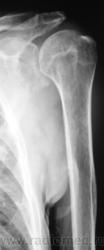

Пациент направлен хирургом на рентгенографию плечевого сустава. Травма, вроде-бы была. Хирург, не мудрствуя, направил пациента на рентгенографию. Пациент предъявляет жалобы на боли в области плечевого сустава, руку поднять не может. Врача-рентгенолога, на момент исследования в рентгеновском кабинете не было.

Вы совершенно правы Татьяна Валентиновна. Я намеренно "обрезал" снимок, произведенный лаборантами, дабы акцентировать внимание на латеральном угле лопатки. Суставная поверхность лопатки и шейка внушают серьёзные подозрения, и с учетом "пороза" и структуры.

Снимок "без обрезания" - ниже. Врача-рентгенолога в кабинете не было, лаборанты, оценив его, начали "пытать" пациента. Оказалось, что флюорографию органов грудной полости, этот пациент, "проходил" лет 5 тому. Ну, и лаборанты приступили к стандартному исследованию органов грудной полости.